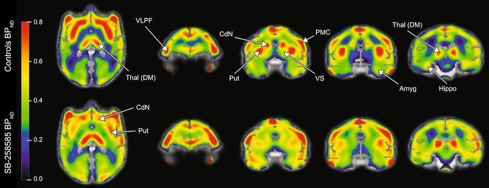

β WAY-208466, a 5-HT6 receptor agonist, increases food motivation in primates: A behavioural and PET imaging study opening perspectives in eating disorders

M. Pitoy, J. Maulavé, L. Gauthier, J. Debatisse, N. Costes, I. Mérida, T. Billard, K. Portier, S. Lancelot, B. Galusca, L. Zimmer, L. Tremblay

Neuroscience Applied 2024, 3, 104086